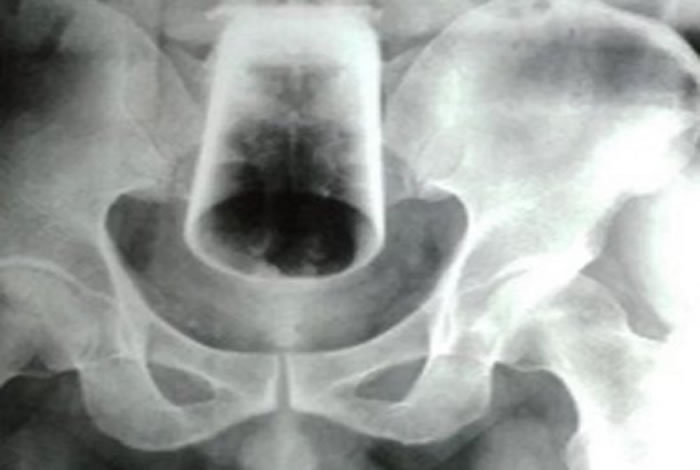

Raio-x - Crédito: Reprodução / Folhamax.com

A vítima foi hospitalizada em Cáceres após um incidente inusitado. Segundo relatos, o homem inseriu o objeto na região anal, e, infelizmente, o copo se quebrou.

Diante da complexidade do caso, o paciente foi transferido para o Hospital Regional de Cáceres e está aguardando uma cirurgia.